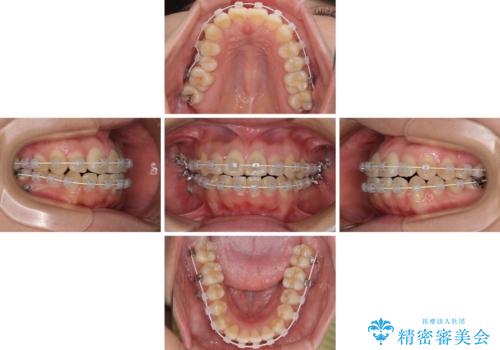

- 審美装置

- 3年6ヶ月

- 30回以上

右奥の歯が180度回転していることで、噛む度にワイヤーに無理な力がかかったようで、頻繁にワイヤーが切れてしまいました。また、下顎を後方に移動させるためのアンカースクリューも脱離することが多く、治療期間が長くなってしまいました。